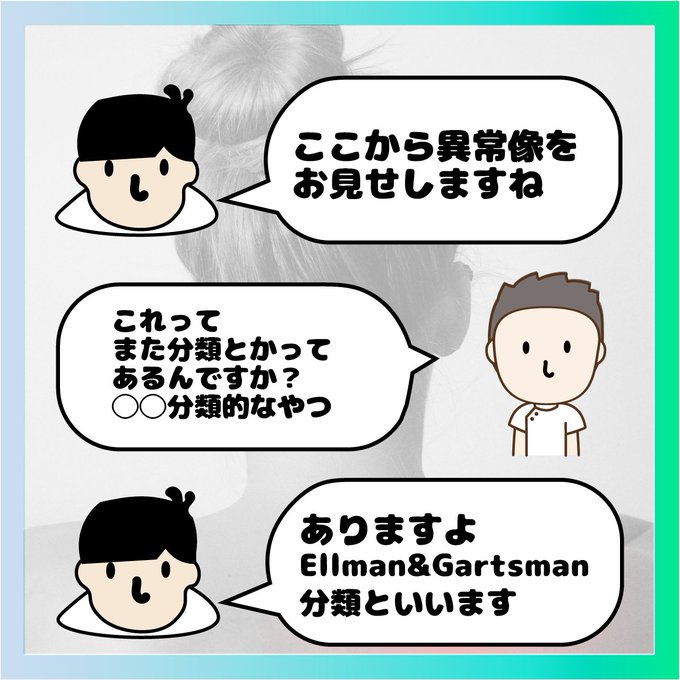

この分類、聞いたことがある〜

と思ってたので今回気合を入れたイラスト作成しましたが

あまり世の中に広がっていないような感じのようです。

いろいろ調べてると

こんなにたくさん分類するんじゃなくて

・三日月型

・U字型

・L字型

の分類が今は一般的な感じでした^^;

腱板の5層構造や断裂の大きさ(1-3-5分類,1-2-4分類)については先日お話しましたが、今回は断裂の「形(shape)」についてです。

腱板断裂には形があります。

・cresent

・L-shape

・Reverse L

・Trapezoidal

・Massive tear

イメージできますか?

僕はなんとなくしか知りませんでした